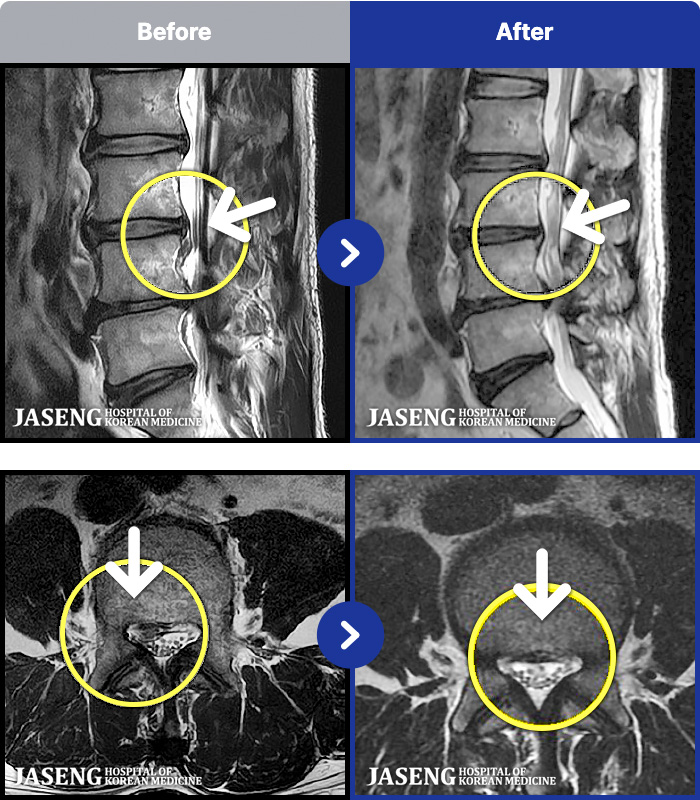

1,268 MRI ũ ʸ Ȯϼ.